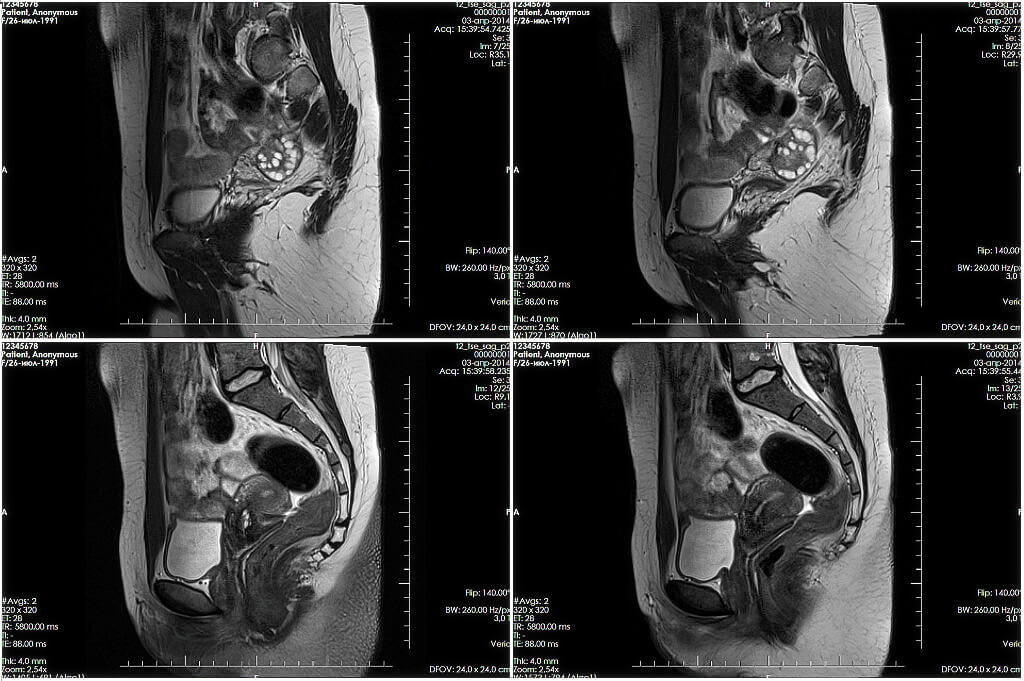

Магнитно-резонансная томография (МРТ)

Магнитно-резонансная томография появилась почти одновременно с компьютерной: в 70-х годах 20 века. Как и КТ, МРТ отображает четкие срезы нужных органов в разных плоскостях в виде контрастных черно-белых картинок и делает возможным получение 3D модели органов. По информативности и точности магнитно-резонансная томография не уступает (и где-то даже превосходит) КТ. По безопасности метод затмевает рентгенодиагностику, так как «не облучает пациентов».

Томограф представляет собой большой магнит определенной мощности. Изображения органов и тканей он строит, оценивая скорость их реакции на электромагнитные волны, которые он излучает. Чаще всего в клинической практике встречаются 1.5 Тл томографы, в большинстве случаев они дают исчерпывающую информацию о структуре тканей и органов. Показания к МРТ обширны. Это и заболевания внутренних органов, и сосудистые нарушения, и опухоли. Но явные преимущества магнитно-резонансная томография имеет при изучении патологий суставов, диагностике заболеваний головного мозга, спинного мозга, органов малого таза.

МРТ определенно перехватил бы пальму первенства у КТ и рентгена, если бы не одно серьезное «но» – исследование проводится в закрытом пространстве и длится больше часа. По этой причине оно не подойдет тяжелым пациентам, людям с клаустрофобией и психическими расстройствами. Процедуру нельзя проводить и тем, у кого есть электронные и металлические конструкции в теле, – электромагнитные волны могут нарушить их работу и положение.